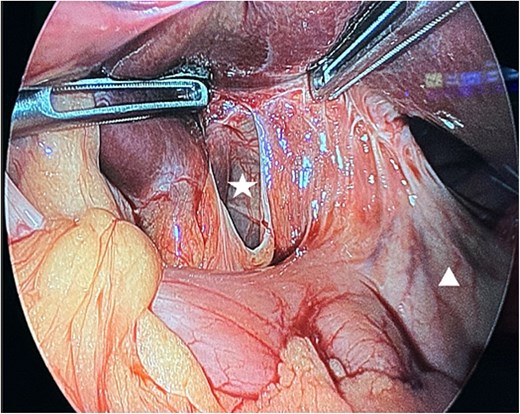

The patient was taken urgently to the operating room for diagnostic laparoscopy. Intraoperatively, a loop of small bowel was found to have herniated through a defect in the lesser omentum. Upon further inspection, the defect was identified in the hepatogastric ligament rather than the foramen of Winslow (Fig. 2). The herniated bowel was released. The bowel appeared hemorrhagic but was still viable. Therefore, resection was deemed unnecessary. The defect was then laparoscopically closed using interrupted sutures to prevent recurrence. The patient had an uneventful postoperative recovery and was discharged home on the third postoperative day.

Intra-operative findings. A defect in the lesser omentum (white star). The stomach (white triangle).